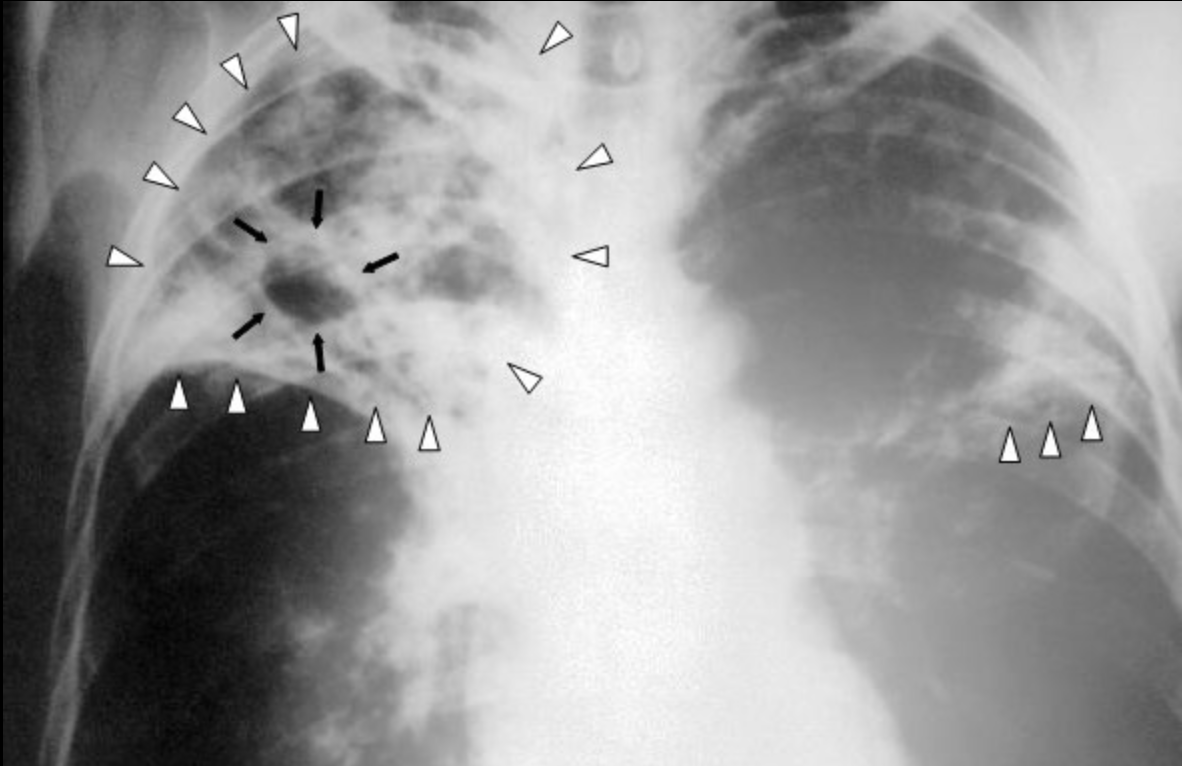

*방사선검사

- 전형적 결핵결절, X 선 검진에서 병변, 투베르쿨린 양성

4) 진단: X 선 검사, 투베르쿨린 검사, 객담배양, 늑막액배양 등